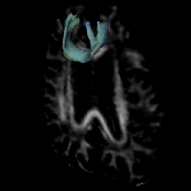

Fig. 4 provides a visualization of our segmentation result. It overlaps with the reference standard in (a) and (c) for FMI and right CST, respectively. The mean test DC of FMI is 0.66 (SD 0.06), that of CST is 0.77 (SD 0.03).

Fig. 4 (b)(d) provide its overlaps with segmented rescan, which was registered by rigidly aligning the FA images. Table 1 gives the reproducibility statistics. Typically, a indicates “substantial” agreement between raters, and a for “almost perfect” [16]. Our mean for FMI longitudinal-segmentations achieved 0.74 and 0.80 for CST. The and show that our method has better reproducibility than reference. Moreover, there was no difference in our longitudinal-measures (FA, MD, volume, paired t-test, ). Our mean FA and MD are consistent with that of the reference. These results show that our method is applicable in longitudinal analysis of WM microstructure.

Fig. 4 provides subject-wise reproducibility in determining diffusion measures. The Bland-Altman plots show that almost all differences are within the limits of agreement and the mean of which is close to zero, indicating no consistent bias in longitudinal-measures. Additionally, Fig. 4 (right) shows that the MD is a discriminative feature for FMI and CST tract.